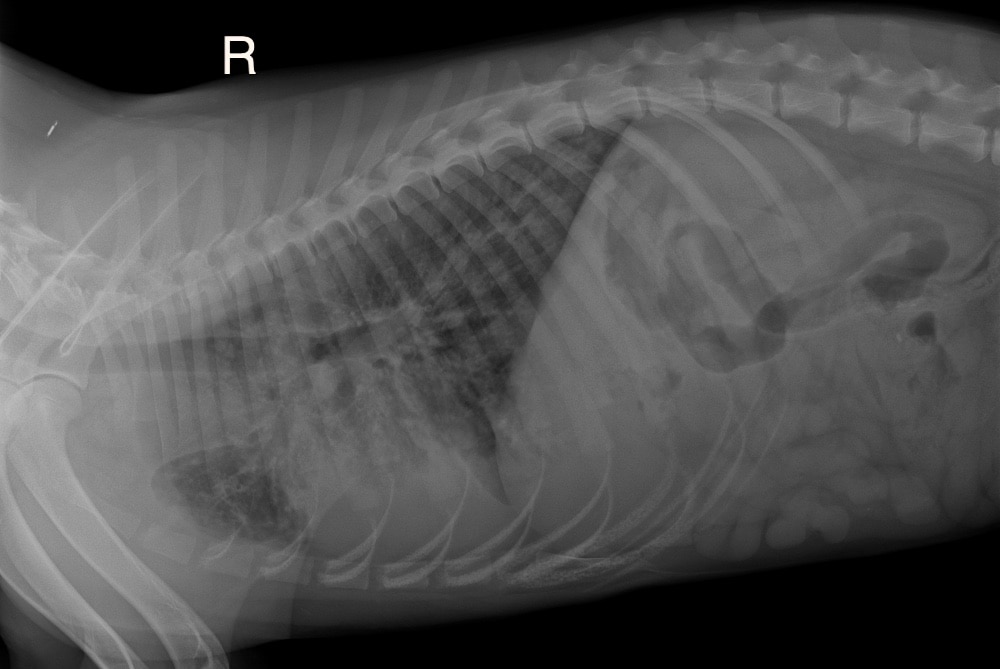

FENRIK ist ein wunderbarer, toller Hund, freundlich, liebenswert und einfach ein toller Gefährte. Leider bringt er gesundheitliche Probleme mit, die nicht zu unterschätzen sind. Laut unserer Tierärztin handelt es sich bei ihm um einen medizinischen Notfall. Bereits als Welpe hatte FENRIK wiederholt mit Lungenerkrankungen zu kämpfen. Es ist daher wahrscheinlich, dass seine Lunge dauerhaft geschädigt sein könnte oder dass er zumindest immer wieder anfällig für Lungenentzündungen bleibt.